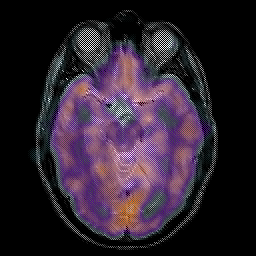

Glioma overlay -- Slice #11

[Home][Help][Clinical] Slice 11